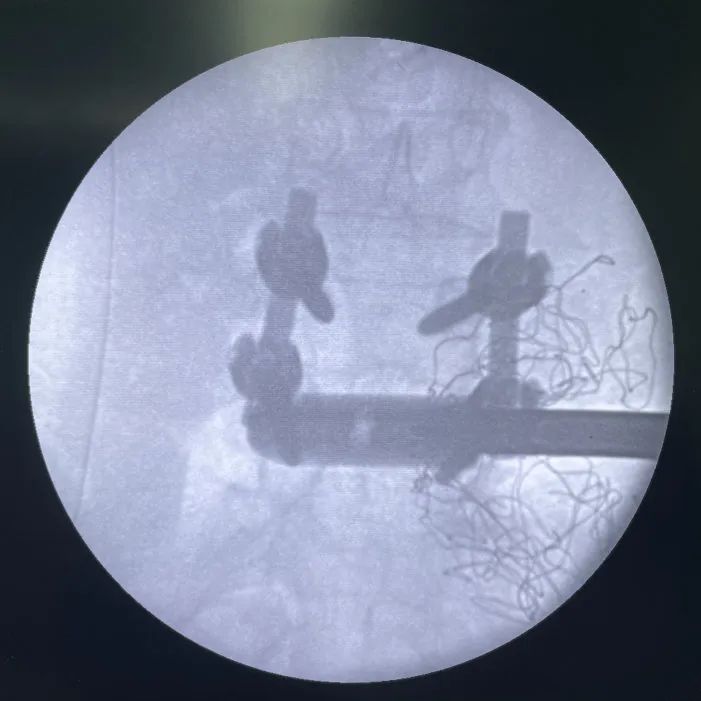

術中影像

- L4/L5植入Uni-L自穩定型腰椎(zhui)融合器(qi)

- 固定夾(jia)植入(考慮患者長期不融合,可能存在終(zhong)板硬化。因此,先使用固定夾(jia)開(kai)路器(qi)預(yu)開(kai)路,再植入固定夾(jia))

正視(shi)圖:頭尾側固定夾均已完全打(da)入

直視圖:cage與固(gu)定夾(jia)完(wan)全打入后

- L3/L4常規OLIF融(rong)合器植入

- 最終透視